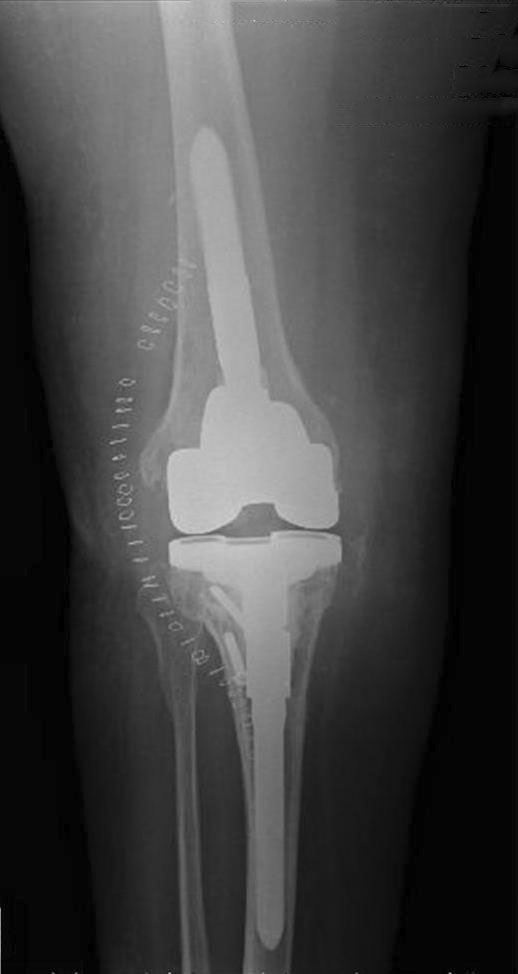

The arthrodesis by intramedullary nail (Figure 8) has gained increasing favour, due to rates of fusion greater than 80% of cases,86,89,90 despite the literature is often based on heterogeneous series of cases secondary to septic or aseptic loosening and bone resection for malignancy.6,91,92

Waldman et al.41 showed the results of a multicenter study on 21 patients treated by modular titanium nail for septic knee arthroplasty loosening followed for 2,4 years (2 to 7.5 years): a solid union was obtained in 20 of 21 patients about 6,3 months after surgery. The authors underline the advantages of this method in contrast to the traditional technique that included the introduction of a long nail from the trochanteric region. The modularity and the morphology of the nails allow it to adapt to different dimensions of the femoral and tibial canal and to facilitate the alignment of the limb. In the presence of bone loss is possible the use of Titanium spacers or bone grafts. Although no patients in this series developed a new infection, the possibility that this event will occur is high, due to the presence of nail. For this reason a two stages protocol is recommended: the initial removal of the prosthesis is followed by nail arthrodesis.82–90

Figure 8 Arthrodesis by intramedullary nail: a) intraoperative images b-c) post-operative x-Ray.